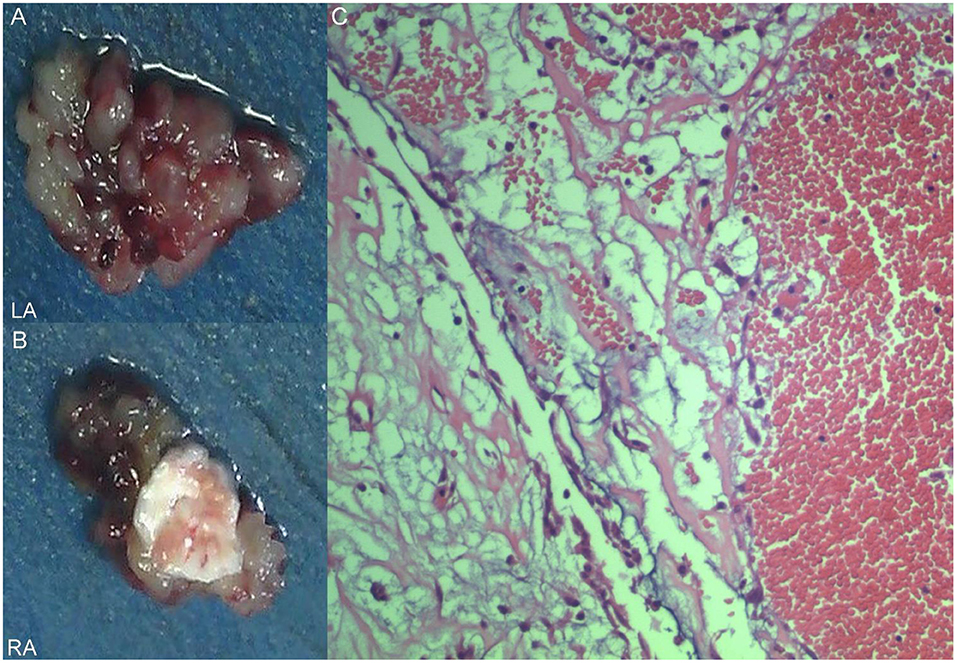

A 17-year-old girl presented to our hospital on August 22, 2021 with clouding of consciousness for more than 3 days. At 3+days prior, the patient was unable to speak the patient was unable to speak when called softly and unable to open the right eye, combined with involuntary movements of the limbs and incontinence. The patient visited the local hospital immediately, where relevant tests were performed, suggesting intracranial lesions. Since the specific treatment measures were unavailable at the previous hospital, she was transferred to our hospital for further treatment. There was no history of trauma or familial genetic diseases, such as high blood pressure and diabetes. Physical examination revealed a body temperature of 37.0°C, heart rate of 110 bpm, regular heart rhythm, blood pressure of 113/77 mmHg, and no pathological murmurs in the valve region; pulmonary auscultation revealed coarse rales in the entire lung. The pupils were equal, round, and pupillary light reflexes were delayed. Both lower limbs exhibited hypertonia and hyperreflexia of the knee and tendon reflexes. Laboratory examinations revealed the following levels (normal range): coagulation function test showed D-dimer was 0.57 mg/L (< 0.5 mg/L) and fibrinogen was 5.82 g/L (2.00–4.00 g/L). Routine blood tests showed that the absolute value of neutrophils was 7.38 × 109/L (1.8 × 109/L−6.3 × 109/L). Infection-related markers showed that the hypersensitive C-reactive protein level was 111.563 mg/L (0.068–8.200 mg/L). Creatine kinase, α-hydroxybutyrate dehydrogenase, and lactate dehydrogenase levels were 148 U/L (26–140 U/L), 218 U/L (90–180 U/L), and 295 U/L (140–271 U/L), respectively. Computed tomography pulmonary angiography (CTPA) detected filling defects in the right atrium, left atrium, and left lower pulmonary basilar artery (Figure 1), and a diagnosis of Pulmonary embolism was made. Transthoracic echocardiography (TTE) revealed irregular iso-echoic masses in the bilateral atrium that were likely myxomas, given their location and appearance in a young patient; the myxoma in the left atrium measured approximately 38 × 21 mm, and it was attached to the junction of the lower part of the interatrial septum (IAS) and the root of the anterior mitral leaflet; in the right atrium it measured approximately 51 × 27 mm, and it was attached to the lower part of the IAS (Figure 2A). These masses resulted in the acceleration of the tricuspid valve antegrade flow (Figure 2B). Craniocerebral computed tomography (CT) showed extensive hypodensity in the bilateral parts of the pons and patchy hypodensity in the left corona radiata area and bilateral basal ganglia areas. Magnetic resonance imaging (MRI) also revealed extensive hypointensity on T1-weighted imaging and hyperintensity on T2-weighted imaging in the bilateral parts of the pons, and a patchy hyperintensity on T2-weighted imaging in the bilateral basal ganglia areas; bilateral centrum semiovale; and right frontoparietal lobe, which presented as high signal on diffusion-weighted imaging (DWI) (Figure 3). This confirmed the diagnosis of brain ischemia. To prevent thrombosis, low molecular weight heparin calcium (subcutaneous injection, 0.4 ml/12 h) was commenced on the second day of admission and continued until discharge. The patient underwent successful removal surgery for a biatrial myxoma. The masses were sent for histological examination, which confirmed the presence of a myxomatous matrix containing myxoma cells (Figure 4). The patient recovered uneventfully and was discharged 9 days after the procedure. The patient has been followed-up postoperatively for over 2.5 months, and limb motor function of the patient has recovered to some degree, but there is intellectual and cognitive decline.

Figure 4. Excised villous biatrial atrial myxoma (A,B) and histology of atrial myxoma. Acid-mucopolysaccharide matrix with characteristic astrocytes and spindle cells which have ovoid nuclei and are surrounded by thin-walled capillaries (Hematoxylin and Eosin, ×200) (C).